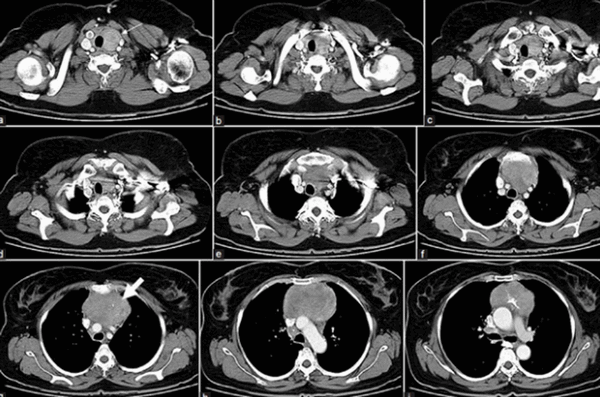

Результат КТ ОГК будет готов через 90-120 минут, в диагностическом центре “Магнит” в СПб полученные данные в сомнительных ситуациях оцениваются коллегиально. Представим на обозрение несколько томограмм, которые демонстрируют патологические процессы в грудной клетке:

КТ органов грудной клетки демонстрирует опухоль средостения (границы выделены маркерами)